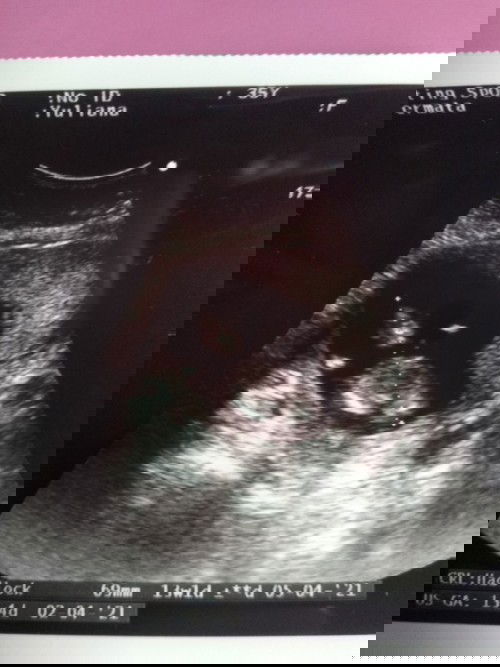

Kehamilan di usia 13-14 week

Sering keram dan sakit perut

Wajar aja selama gak ada flek, krna janin dan rahim makin berkembang